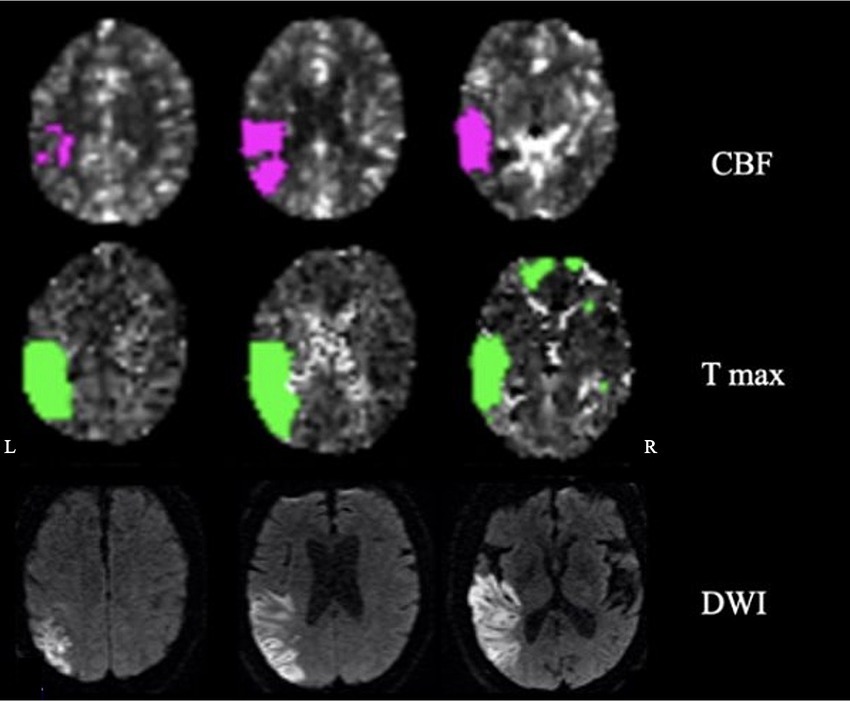

The patient was a 72-year-old man with a history of atrial fibrillation and abdominal aortic aneurysm repair presenting with a wake-up stroke with right-sided weakness and facial drop, and aphasia. CT with perfusion and angio-CT at 3.5 h from onset showed infarct in the left middle cerebral artery (MCA) territory (mismatch volume of 62 mL and ratio of 2.3) with a left MCA thrombus. Neuroimaging was reviewed by two neurologists; the ischemic core involved the following regions: superior and middle temporal gyrus (excluding the pole), inferior parietal lobule and supramarginal gyrus, posterior insula, and entorhinal cortex. The penumbra region extended to the inferior temporal gyrus including the pole, superior parietal lobe, and parahippocampal (Figure 1).

Figure 1. Neuroimaging: cerebral blood flow (CBF), time-to-maximum (Tmax), and diffusion-weighted imaging (DWI) showing penumbra and ischemic regions.

The patient underwent thrombectomy and arterial tissue plasminogen activator (tPA). On day 3, at the neurological examination, there were mild weakness of the right upper extremity, expressive and receptive aphasia, spatio-temporal disorientation, and right-side hemispatial and body neglect. The MRI on day 4 confirmed residual ischemic damage of the left inferior parietal lobule, temporal lobe (excluding the pole), and posterior insula (Figure 1).

In the patient, the ischemic lesion involved the left temporal lobe (but not the temporal pole) and the adjacent inferior parietal lobule (Figure 1). The power spectrum analysis of HD-EEG revealed a significant asymmetry between the two hemispheres with predominant delta and theta activity (p < 0.05) over the lesioned hemisphere. Both scalp topographical analysis and source reconstruction provided evidence for an increase in delta activity bilaterally in ventral regions (including the temporal poles) and the superior parietal lobules and in the left post-central gyrus (Figures 2, 3).